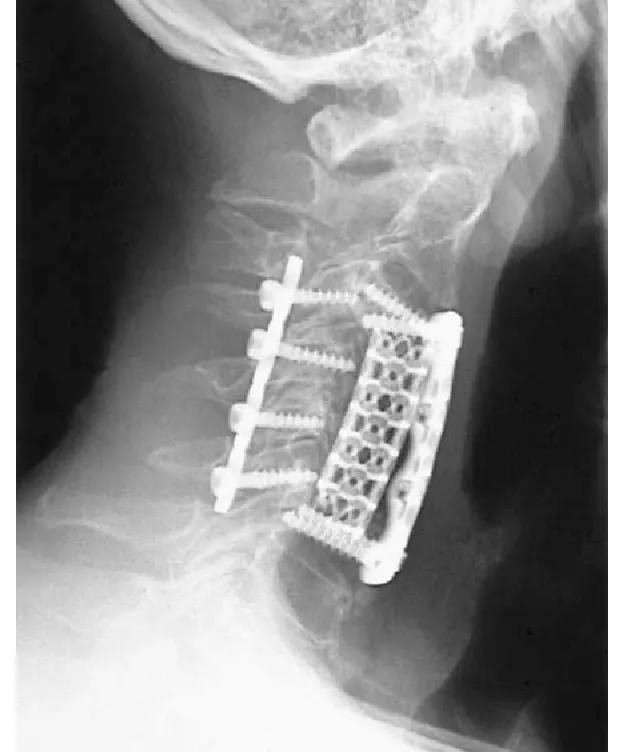

ထို့အပြင်၊ တိုက်တေနီယမ်ကျောရိုးအိတ်များသည် ပုံသဏ္ဍာန်အမျိုးမျိုးနှင့် အရွယ်အစားအမျိုးမျိုးဖြင့် ရောက်ရှိလာပြီး သမားတော်များသည် ကျောရိုးရှိ ကျောရိုးကို ပိုမိုကောင်းမွန်စေရန် လိုအပ်သလို လိုအပ်သလို သင့်လျော်သော ပုံသဏ္ဍာန်နှင့် အရွယ်အစားသို့ ပုံသွင်းနိုင်မည်ဖြစ်သည်။ တိုက်တေနီယမ် ကျောရိုးလှောင်အိမ်သည် ခွဲစိတ်ပြီးနောက် ကြည့်ရှုခြင်းနှင့် စစ်ဆေးခြင်းအတွက် ကောင်းမွန်သော X-ray ပွင့်လင်းမြင်သာမှုရှိသည်။

တိုက်တေနီယမ်ကျောရိုးလှောင်အိမ်အား အသုံးပြုရာတွင် ခွဲစိတ်ဆရာဝန်သည် လှောင်အိမ်အား ကျောရိုးနေရာအတွင်းသို့ ထည့်သွင်းပြီး အရိုးကြီးထွားမှုနှင့် ကျောရိုးတည်ငြိမ်မှုကို မြှင့်တင်ရန်အတွက် အရိုးပြာ သို့မဟုတ် အရိုးအတုဖြင့် ဖြည့်သွင်းပေးသည့် ခွဲစိတ်မှုလိုအပ်သည်။ ခွဲစိတ်ပြီးနောက် လူနာများသည် implant fuse ကိုပိုမိုကောင်းမွန်စေပြီး ကျောရိုးကိုပုံမှန်လုပ်ဆောင်မှုကိုပြန်လည်ရရှိရန် သင့်လျော်သောပြန်လည်ထူထောင်ရေးများပြုလုပ်ရန်လိုအပ်ပါသည်။